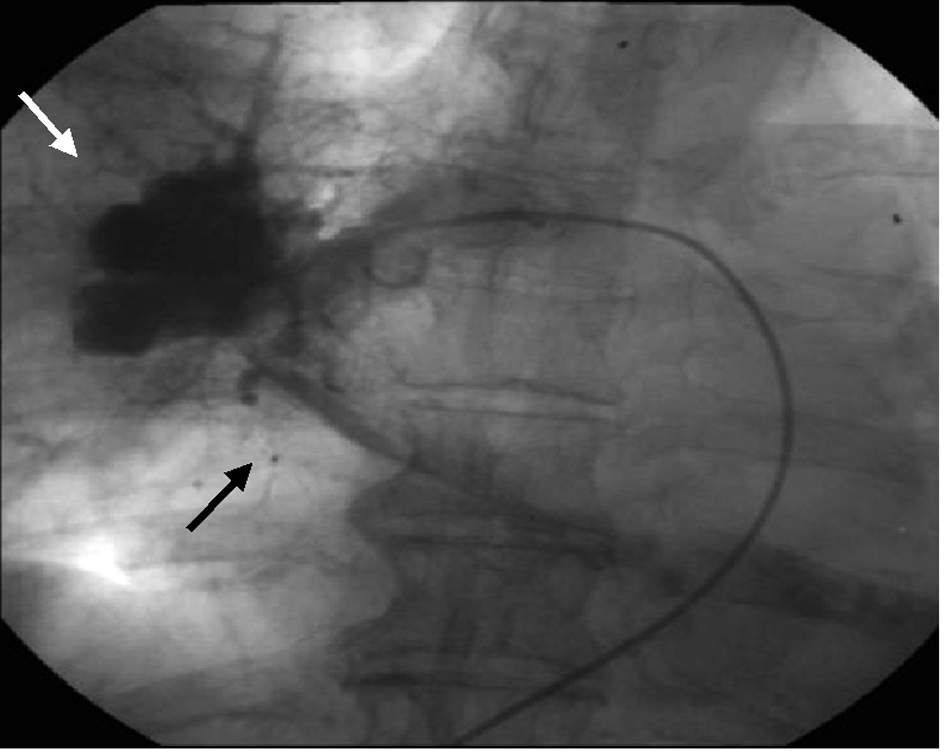

TTE revealed dilatation of the main pulmonary trunk and high systolic pressure gradient across the tricuspid valve of 49 mmHg that is consistent with pulmonary hypertension. There was a thrombus-like mass in the right pulmonary artery and around the left atrium. CT scan similarly revealed a large mass in the proximal portion of right pulmonary artery and around the left atrium, but no abnormal mass detected in the lung and other organs (Fig. 1). However, lung scintigraphy demonstrated little visualization of the right lung on technetium-99m macroaggregated albumin (99mTc-MAA) perfusion scan. Ventilation scan with krypton-81m (81mKr) gas was normal (ventilation-perfusion mismatch). Cardiac catheterization demonstrated mean pulmonary artery pressure of 40 mmHg that indicated pulmonary hypertension. Right pulmonary angiography demonstrated vascularized mass with a fistula from the right pulmonary artery to the left atrium (Fig. 2). To confirm this suspected malignant features and the extent of disease, 18-fluorodeoxyglucose positron emission tomography (FDG-PET) was performed. FDG-PET revealed a large mass at the area of the right pulmonary artery and the bilateral atira with intense uptake of FDG. The maximum standard uptake value (SUVmax) was 25.2. No other undue hypermetabolic lesions were noted elsewhere (Fig. 3).

![]() Click for large image | Figure 2. The image of right pulmonary angiography. Vascularized mass (white arrow) with a fistula from the right pulmonary artery to the left atrium (black arrow). |